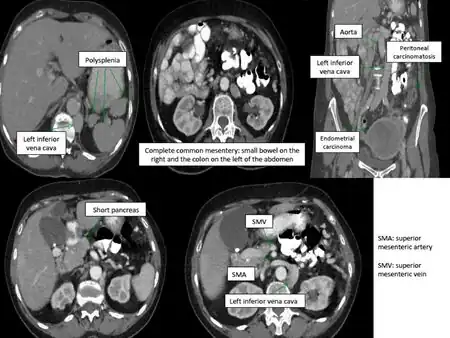

Situs ambiguus is a rare congenital defect in which the major visceral organs are distributed abnormally within the chest and abdomen. Clinically heterotaxy spectrum generally refers to any defect of Left-right asymmetry and arrangement of the visceral organs; however, classical heterotaxy requires multiple organs to be affected. This does not include the congenital defect situs inversus,[1] which results when arrangement of all the organs in the abdomen and chest are mirrored, so the positions are opposite the normal placement. Situs inversus is the mirror image of situs solitus, which is normal asymmetric distribution of the abdominothoracic visceral organs. Situs ambiguus can also be subdivided into left-isomerism and right isomerism based on the defects observed in the spleen, lungs and atria of the heart.

Abdominal organs, including the liver, stomach, intestinal tract, and spleen may be randomly arranged throughout the left-right axis of the body. Distribution of these organs largely dictates treatment, clinical outcomes, and further evaluation.

Random positioning of the stomach is often one of the first signals of situs ambiguus upon examination. Malrotation of the entire intestinal tract, or improper folding and bulging of the stomach and intestines, results in bowel obstruction. This impairment leads to vomiting, abdominal distension, mucus and blood in the stool. Patients may also experience abdominal pain. Intestinal malrotation is more commonly identified in patients with right atrial isomerism than in those with left atrial isomerism.

Isomeric patients often experience disruptions to splenic development during embryogenesis, resulting in an overall lack a spleen (asplenia) or development of many spleens (polysplenia). Asplenia is most often observed in patients with right atrial isomerism. Polysplenia results in 90% of patients with left atrial isomerism. Although they have many spleens, each is usually ineffective resulting in functional asplenia. Rarely, left atrial isomeric patients have a single, normal, functional spleen. Patients lacking a functional spleen are in danger of sepsis and must be monitored.[2]

- Vascular abnormalities:

- Interrupted inferior vena cava,

- Bilateral superior or inferior venae cavae

- Intrahepatic interruption of the inferior vena cava with connection to the azygos or hemiazygos veins

- Aberrant portal veins.